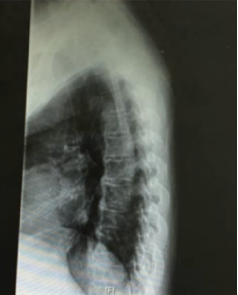

胸椎X线检查:多个胸椎只有右侧缘肥大骨赘骨桥形成

相对而言,这个病例倒是比前者“实诚”很多,虽然患者有腰背部疼痛的症状,但是检查结果既没有炎性指标的升骶髂关节也无明显异常,唯一特别的是患者胸椎的X线改变。

但诊断其实也没那么难,从患者的侧位X线可以看出其并不是AS特征性的骨桥形成(即接近垂直状态),正位X线中也可以看出其并非是对称性的竹节样改变,该名患者的多个胸椎只有右侧缘肥大骨赘骨桥形成。